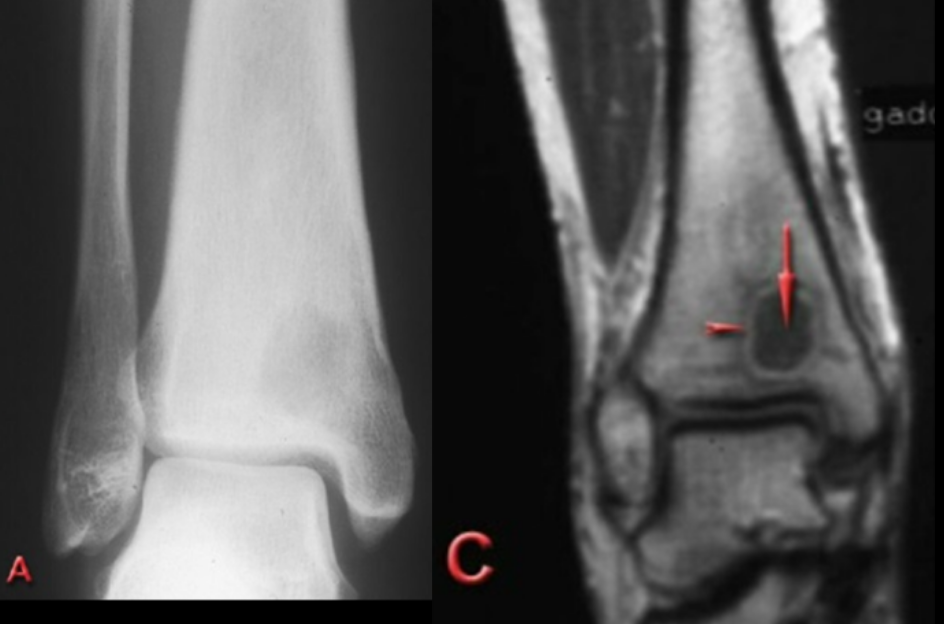

7-year-old male with leg pain, swelling, and a fever has normal x-rays.

This is a T1 fat suppression MRI with contrast.

What is the diagnosis?

A

Osteomyelitis

medullary cavity infection with cloaca